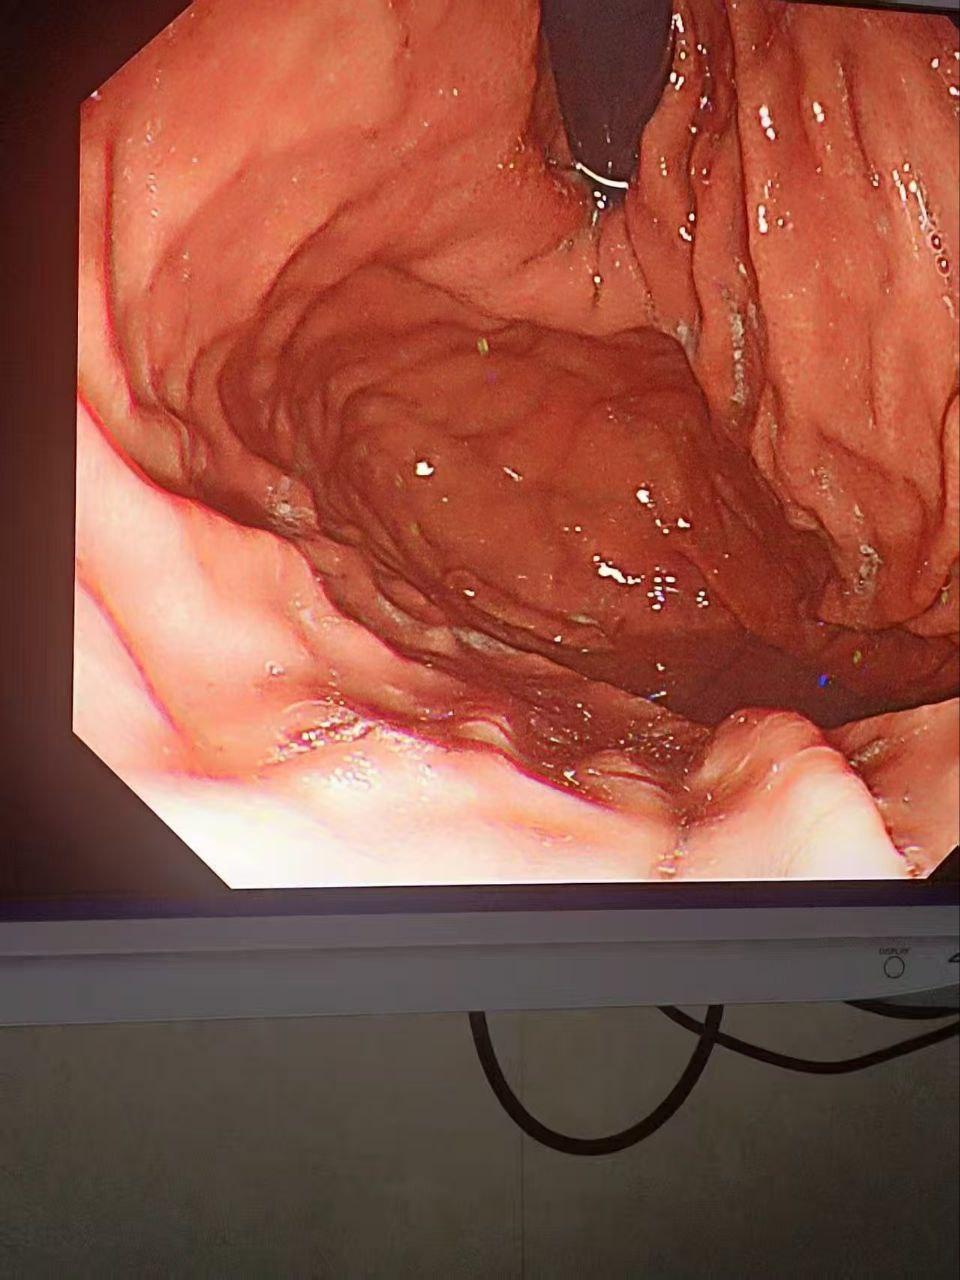

金主酒吧消费巨款,陪酒女为博金主一笑,脑子一热跟金主玩酒后抠屁眼,现场有姐妹看着,但不料还是玩大了,金主爸爸狂抠,不料戒指掉进屁股里找不到了,事后才发现顺着小肠进去了,你们有钱人玩的真花呀。